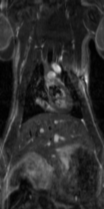

脳内点状出血など特殊な対象の例

ラット脳の出血性ストロークの画像

右の側頭部の出血に伴い、同部位での信号強度が上昇しています。

(Insight neuroimaging のご好意により掲載)